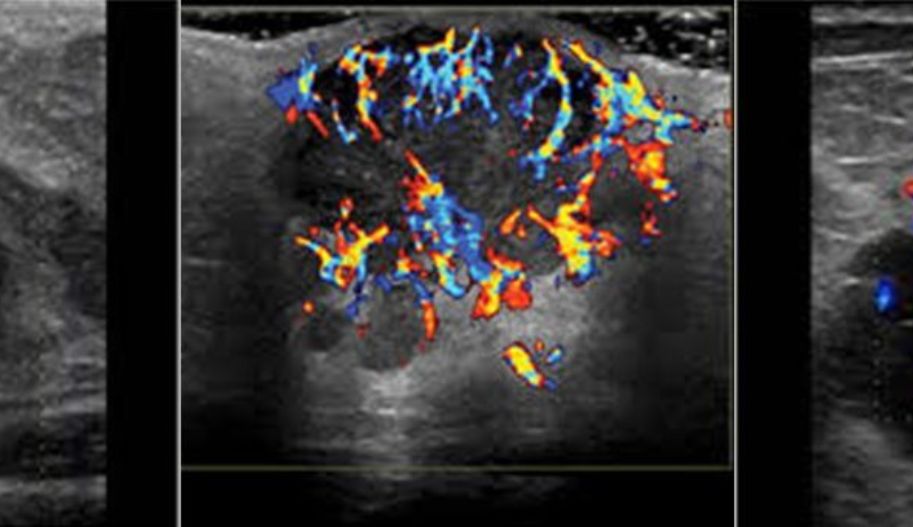

The cost of breast ultrasound and color Doppler is similar to that of mammography and much lower than breast MRI. Color Doppler specifically helps identify blood vessels around and within mass lesions.

The presence of blood vessels can be an additional criterion in distinguishing between benign and malignant masses, though it is not sufficient on its own to characterize a lesion. Moreover, color Doppler is useful during ultrasound-guided biopsy to determine the path of vessels and avoid passing the needle through them.